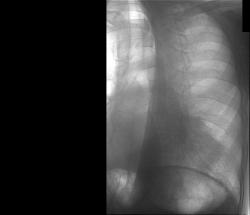

Первое исследование - цифровая флюорография, зарегестрировано как профилактическое (возможно ошибочно). Заключение - спайка в лев косто-диафрагмалном синусе, других изм. не выявлено.

Через 10 дней направлен повторно, диагноз - пневмония слева. Прямой снимок без признаков инфильтрации, учитывая клинику (интоксикация, гектическая температура, боль в лев. половине гр. кл.), решили посмотреть за сердцем в лев. косом положении, лев. боковой сам Бог велел (снимки представлены). Посмотрели и скопически: в S10 инфильтрация с участками просветления, в заключении написали - пневмония, но термин "абсцедирование" решили не применять, хотя "в уме держали". Больного направили в т/о, там почему-то усомнились в нашей диагностике, пациент вернулся: "меня направляют на Р-гр". Пришлось связаться с терапевтами и прочитать лекцию о том, кто и за что отвечает. На следующий день терапевты с завидным упрямством настаивают на контрольной Р-гр., говорят - боимся абсцедирования, хорошо - говорю, договариваюсь с кэтэшниками, "прокатили" грудную клетку. Но ничего нового, дополнительного не нашли, а "просветлениями" оказались просветы бронхов. Инфильтрация расположена пристеночно, прилежит к позвоночнику с переходом на заднюю стенку гр. клетки, именно в связи с этим никак не прявляет себя на прямом снимке и на боковом выглядит не слишком убедительно. Наиболее оптимальными для такого расположения являются передняя левая или задняя правая косые проекции. Еще через 10 дней, при контрольной рентгеноргафии (прямая и левая боковая), картина без признаков инфильтрации, зная особенности случая, беру за экран и при указанных выше положениях вижу остатки инфильтрации, трактую как "остаточные изменения после пневмонии". Клинически - пациент бъет себя в грудь: "все прекрасно, домой хочу!".

Достал и прикрепил первичную флюорограмму (beg), сделана за 10 дней до нижеследующих. Мне кажется на ней угадывается тень за сердцем, на уровне головки 9 р.?